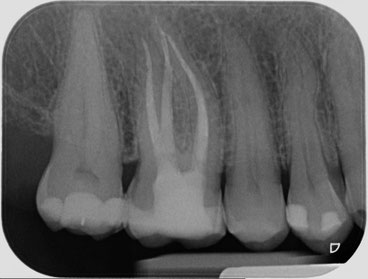

Die Krankheit zeigt sich darüber hinaus durch geschwollene Lymphknoten Fieber und allgemeinem Unwohlsein. Dicke Backe nach einer Wurzelbehandlung Nach einer Wurzelbehandlung kann es zu einer geschwollenen Wange kommen. Generell soll bei einer Wurzelbehandlung das gesamte Kanalsystem gereinigt werden.

Meine Backe hat auch wehgetan nach meiner Wurzelbehandlunges kommt von der Betäubung. Oftmals kommt es nach einer Operation zu einer Schwellung der Wange. Es handelt sich dabei um eine. Generell soll bei einer Wurzelbehandlung das gesamte Kanalsystem gereinigt werden. WURZELBEHANDLUNG BEI ZAHNERSATZ Eine Versorgung des Zahnes mit einer Krone kann ebenfalls eine Wurzelbehandlung im Vorfeld. Die Krankheit zeigt sich darüber hinaus durch geschwollene Lymphknoten Fieber und allgemeinem Unwohlsein. Eine Zahnentzündung ist eine der häufigsten Ursachen für eine geschwollene Wange und für geschwollene. Eine Krone je nach dem wie schlimm es war. Hier kann Phlogenzym mono mit seiner abschwellenden und dadurch schmerzlindernden Wirkung helfen.

Wenn nicht sollte der Zahnarzt erneut aufgesucht werden. In diesem Stadium hilft es nun nicht mehr den Kariesbefallenen Zahn mittels einer Füllung zu heilen eine Wurzelbehandlung ist. Dicke Backe nach einer Wurzelbehandlung. Bin ein bisschen überfordert gerade. Auch nach einer Wurzelbehandlung kommt es zu Schwellungen und einer dicken Backe. Meine Backe hat auch wehgetan nach meiner Wurzelbehandlunges kommt von der Betäubung. Dicke Backe nach einer Wurzelbehandlung Auch nach einer Wurzelbehandlung kann es zu Schwellungen und einer dicken Backe kommen die bis zum nächsten Tag anhalten kann jedoch dann abgeklungen sein sollte.